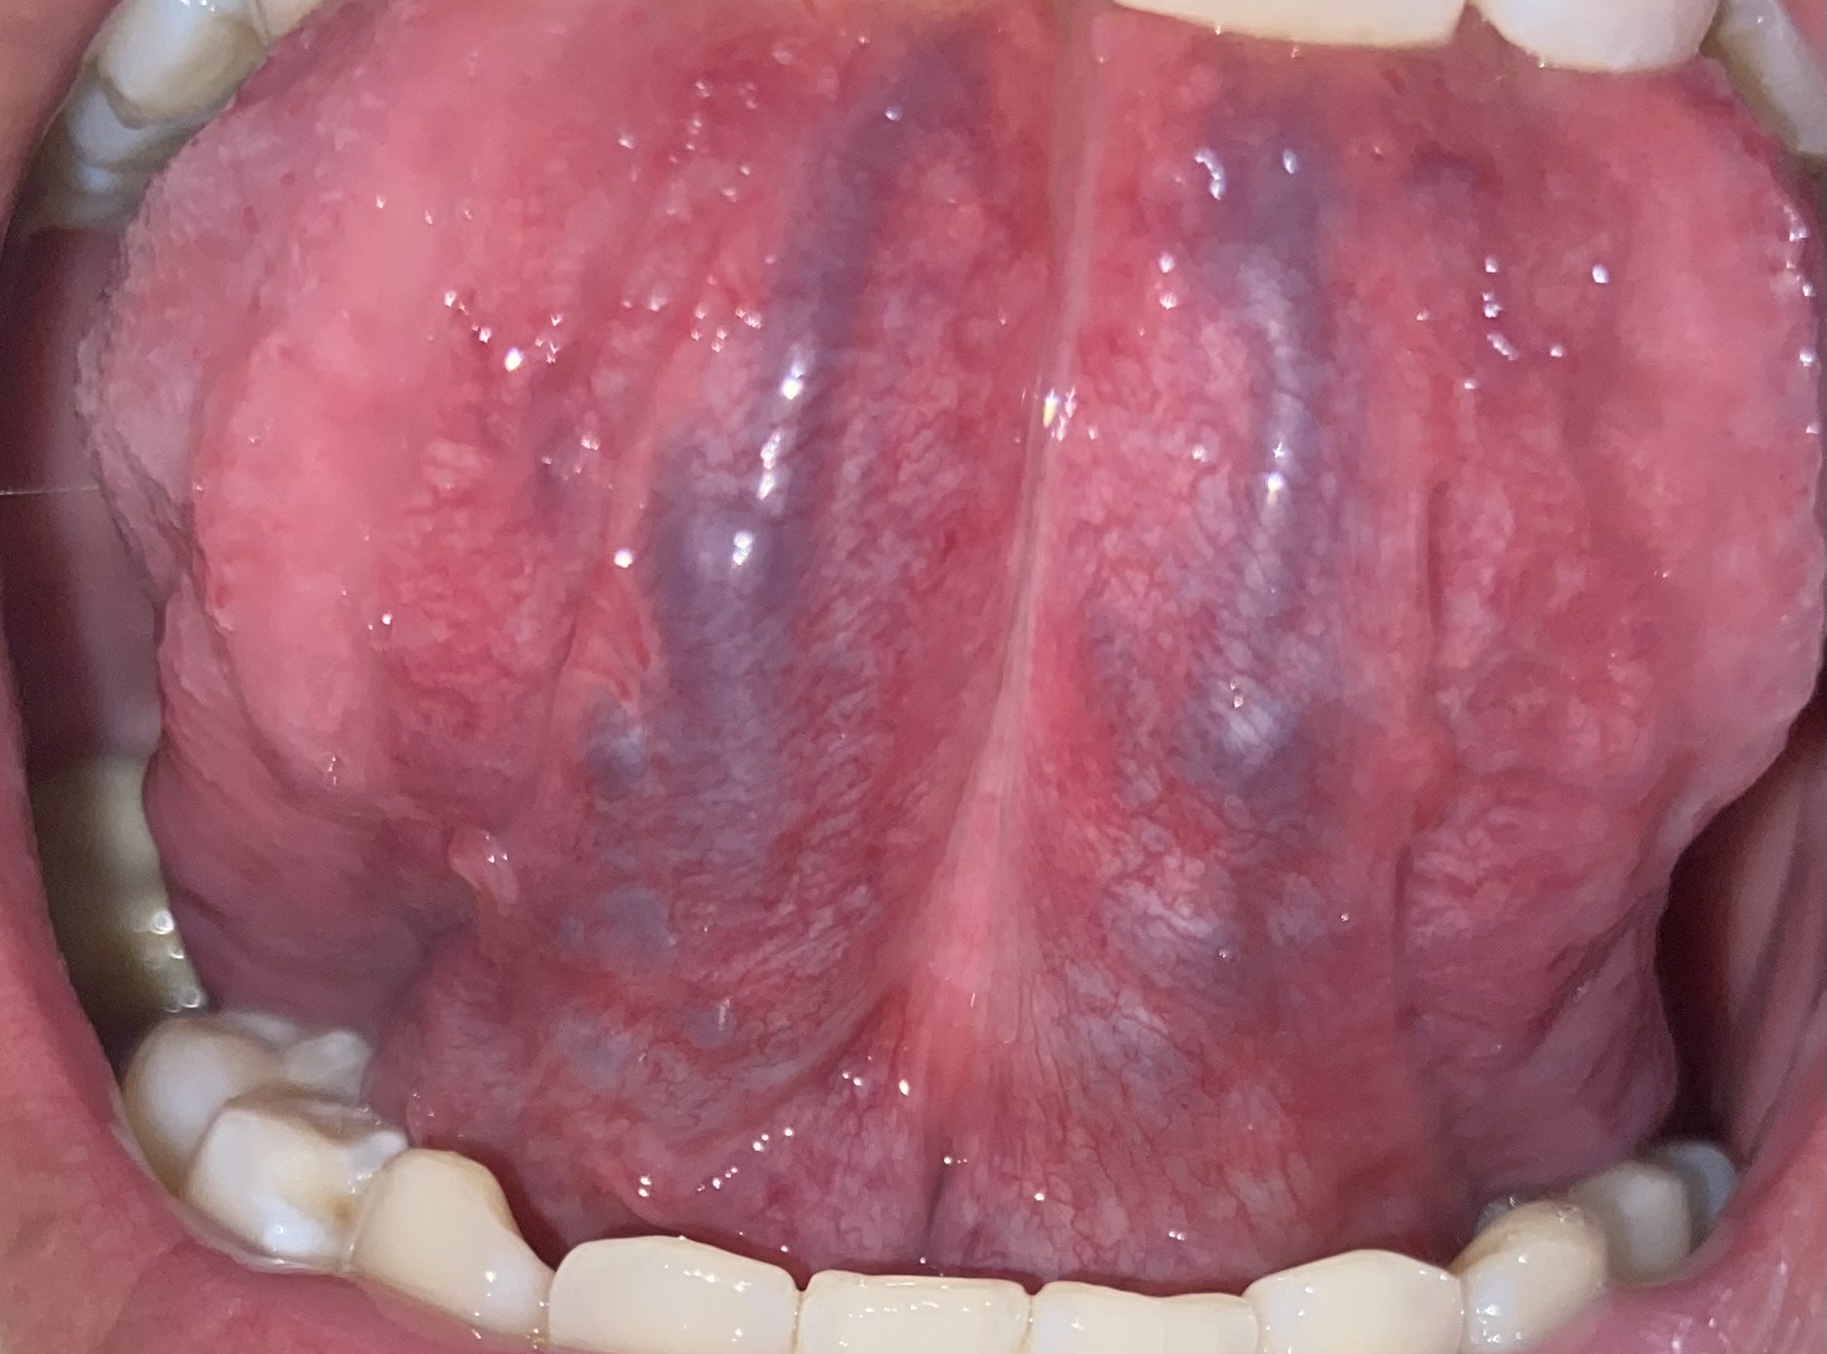

Bác sĩ cho em hỏi đây có phải nếp gấp dưới lưỡi không ạ. Em xin cảm ơn các bác sĩ.

Lưỡi em bình thường em ạ. Nó là nếp gấp và cấu tạo của lưỡi em ạ